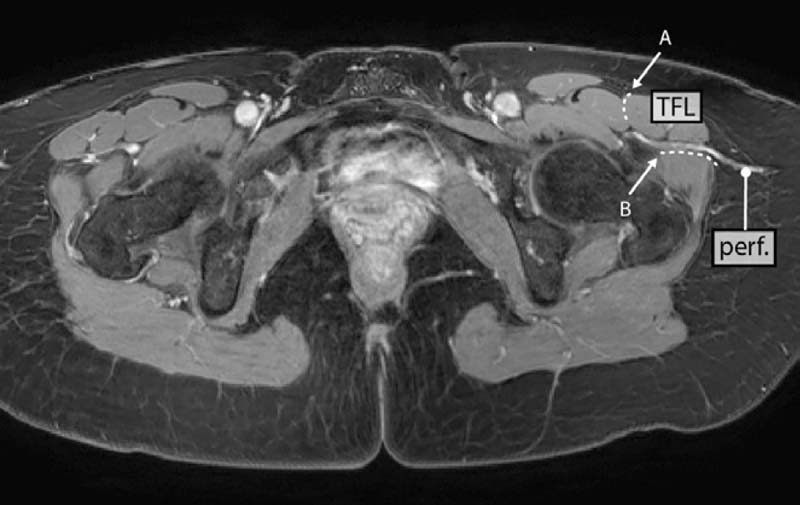

The TFL compartment arises from the outer edge of the iliac crest, between the lateral surface of the anterior superior iliac spine (ASIS) and the iliac tubercle. The TFL compartment is lined by the gluteus medius/minimus compartment posteriorly and by the rectus femoris/vastus lateralis compartment anteriorly. The joined borders between these three compartments are the posterior and the anterior intermuscular septum ( Fig. 13.1 ).2

The TFL perforators have been studied by anatomic dissection, cross-sectional imaging, and clinical studies.2,4–12 Septocutaneous perforators may run in the anterior or posterior intermuscular septum. Due to the anatomic variability of the vasculature, confusion arose in the past about blood vessel and flap terminology. The TFL perforator flaps can be divided into three categories based on the location of the perforators from the ascending branch of the LCFA ( Fig. 13.2 ):

The anatomy of the LCFA and its branches is quite variable.4,13,14 However, a septocutaneous perforator originating from the LFCA is always present in the posterior septum between the TFL muscle and the gluteus medius/minimus muscles2 (type 3 flap). The type 3 flap, named the lateral thigh perforator (LTP)* flap or septocutaneous (sc)-TFL flap for simplicity, is advantageous for reconstruction because of its straightforward dissection and usually large-caliber vessels. The preoperative planning and the operative dissection are described in the following sections.

Every patient undergoes preoperative imaging with magnetic resonance angiography (MRA) using the protocol previously described.15 The septocutaneous perforators are identified ( Fig. 13.3 ). The distance, in a sagittal plane, of the perforators from the ASIS or pubic tubercle is measured. A handheld Doppler is used to confirm perforator locations, and which are marked on the skin surface.